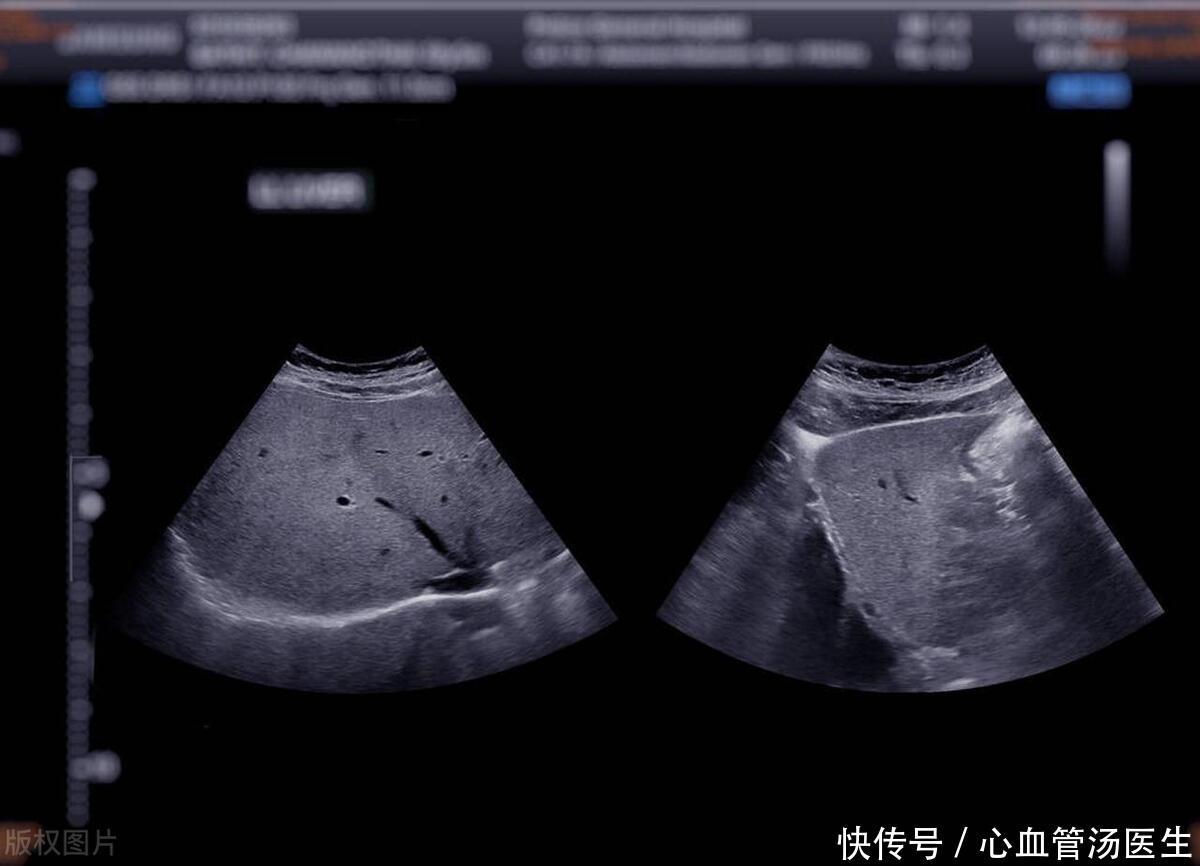

体检报告3项高,不看彩超就知道很可能是脂肪肝,3大危害